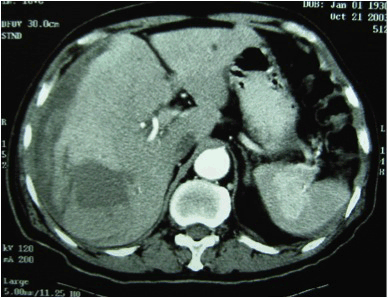

A 73-year-old male presented to a public hospital with acute onset paraumbilical pain for the preceding few hours. His past medical history was unremarkable and there was no documentation on the immune status or being labeled as human immunodeficient virus (HIV) carrier. He had not taking any regular medications including steroid. Subsequent chest and abdominal radiographs and blood investigations were grossly normal. Within a few hours after admission, the patient complained of deterioration of his symptoms, and interval physical examination elicited tenderness and guarding over the right upper quadrant. A diagnostic laparoscopy was arranged promptly, and 500 mL of liquefied old blood was found inside the peritoneal cavity. On further examination, there was a 5-cm subcapsular hematoma at segment V of the liver. The procedure was converted to a formal laparatomy for a more detail examination but there was no additional finding. Other intra-abdominal organs including the spleen were all normal. Peritoneal lavage with normal saline was performed and it was decided to manage the liver hematoma conservatively. The abdominal wound was then closed. After the operation, the patient recovered smoothly and was discharged after four days. Unfortunately, one week after his discharge, he presented again with acute onset of epigastric pain. Computed tomography (CT) scan of the abdomen revealed a large subcapsular hematoma with an associated intra parenchymal hepatic hematoma in segments VI/VII. (Figure 1) An emergent angiogram was performed which did not demonstrate an active bleeding source. Transarterial embolization of the right hepatic artery was performed. After the procedure, his hemoglobin continued to drop and he developed hypotension. Emergency laparotomy found 1800 mL of blood inside the peritoneal cavity. A right hepatectomy was performed in light of recurrent hemorrhage and presence of hepatic subcapsular hematoma. The appearance of the surgical specimen is shown in (Figure 2). The patient remained stable after the operation until the 7th day when he developed sudden onset of hypovolumic shock again. Emergency re-laparotomy revealed 1500 mL of fresh blood within the peritoneal cavity. On this occasion, there was bleeding noted from the spleen with rupture of the splenic capsule. Splenectomy was performed for hemostasis and the rest of the laparotomy was normal. The surgical specimen of the spleen is shown in (Figure 3). Postoperatively, the patient was nursed in the intensive care unit (ICU). However, he developed liver and renal failure with associated sepsis. Despite maximal support, he succumbed two weeks afterwards because of multi-organ failure. Histopathological examination of the liver and splenic specimens showed 'Pools of blood within the parenchyma intermixed with fibrin' confirming the diagnosis of peliosis hepatis and splenosis. | ||||||

Peliosis affects parenchymatous organs and most commonly involves the liver. The condition is also known to occur in the lymph nodes, bone marrow, lungs, parathyroid gland, kidneys and as illustrated in our case, also the spleen. [3] This is a rare disorder and the reported incidence is 0.13%. [4] The presenting signs and symptoms are variable and generally non-specific. They range from asymptomatic and diagnosed incidentally to fatal outcomes. The patient of the present report presented with spontaneous rupture of the target organs causing hemoperitoneum and unfortunately resulted in mortality. Hepatomegaly, icterus and fever were the main and characteristic symptoms in extensive peliosis reported in literature. [5] The exact cause for peliosis is unknown but is associated with wasting conditions such as tuberculosis, acquired immunodeficiency syndrome (AIDS), post-transplant immunodeficiency, malignancies and hematological disorders. [6] Recent reports also show a strong association with medications including steroids, oral contraceptive pill, adrenal androgens and azathioprine. [7] In the present case, the diagnosis of peliosis was not suspected throughout the treatment course and therefore no investigation was performed to delineate the possible underlying causes. Only when the pathological results confirmed the diagnosis had the surgeons retrospectively review the case history. It was found that this patient was not put on any medications including steroid, immunosuppressant, contraceptive pill, adrenal androgens or azathioprine and none of those associated conditions was identified. Several theories exist regarding the pathogenesis of peliosis. Some favor congenital malformation of vessels or microcirculatory disturbances secondary to altered intravascular pressures for the development of the disease. [8] [9] [10] Others suspect that it is an acquired vascular disorder resulting from a toxic trigger (i.e., drugs). [11] [12] Radiological diagnosis is possible but findings are variable depending on the pathological patterns of the underlying disease and various stages of the blood components. Features on CT scan or magnetic resonance imaging (MRI) scan mimic those of hepatocellular carcinoma, a hypervascular metastases or hemangioma. [13] [14] [15] Peliosis should be considered when focal liver lesions exhibit radiological features of homogeneously high and persistent enhancement, slow centripetal enhancement, or persistently low enhancement. [16] In the present case, the CT scan was a standard emergent scanning and was different from the standard three-phrase scan for diagnosis of hepatocellular carcinoma. It revealed a hepatic intra-parenchymal and subcapsular hematoma, (Figure 1) . South-East Asia is an epidemic area for hepatocellular carcinoma and therefore, the diagnosis based on the CT scan at the time of presentation was ruptured hepatocellular carcinoma. Treatment options are determined by the underlying cause. When peliosis is caused secondary to medications, cessation of the offending medications can lead to regression. [4] This was not present in our patient. For patients presenting with rupture and subsequent intra-abdominal hemorrhage can be treated effectively with transarterial embolization, [17] which was one of the initial treatment modalities in our patient. The bleeding source was not identified in the angiogram and the hemodynamics continued to deteriorate that necessitated an emergent right hepatectomy. Before the formal pathology report was available, which could have guided the authors to search for other potential involving organs such as the spleen, our unfortunate patient had spontaneous rupture of the spleen. This episode became another massive hemorrhagic insult to our patient and subsequently ended in multi-organ failure. Although peliosis is a rare disease entity, one should have a high index of suspicion as one of underlying causes for spontaneous hemoperitoneum when common etiologies cannot account for the clinical picture. Retrospectively, splenectomy at the time of hepatectomy could have saved the patient for the second hemorrhagic insult but whether it was an appropriate decision at the moment of hepatectomy remained to be discussed. Liver transplantation is another reported therapeutic option for those who present with irreversible liver insufficiency and cirrhosis. [18] | ||||||